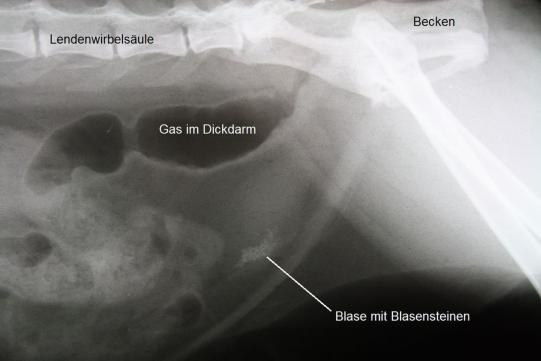

Unter Ultraschallkontrolle wird steriler Urin direkt aus der Blase entnommen und in einem externen Labor bakteriologisch untersucht - es werden aber keine Erreger festgestellt. Hingegen zeigt sich im Ultraschall, dass die Blase Fremdkörper enthält, welche einen Schallschatten werfen. Im Röntgen bestätigt sich die Vermutung, dass die Blase der Katze eine grosse Zahl sehr kleiner Steine enthält, welche röntgendicht ("weiss") erscheinen.

Es muss angenommen werden, dass die Katze aufgrund der mechanischen Blasenreizung durch die kleinen Blasensteine die beobachteten Symptome zeigt. Eine chirurgische Entfernung der Steine erscheint wenig erfolgversprechend - die Steine sind so klein, dass sie sich problemlos in den Falten der geschwollenen Blasenschleimhaut verstecken können und so dem Auge und dem Tastsinn des Chirurgen entgehen könnten.